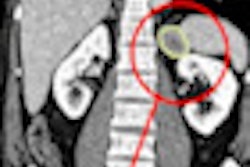

Against this background, please take a look at our new CT Digital Community, which launches officially this week. In this special section of our site, you will find news from the latest congresses, including a new study presented at the International Society for Computed Tomography meeting that found CT can predict cardiovascular events in symptomatic patients, as well as information about how CT reveals gender differences in metabolic syndrome, and new breast CT research.